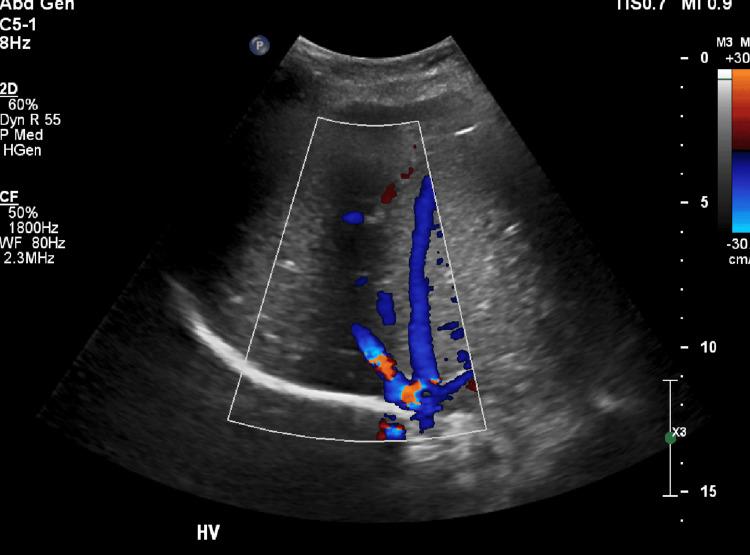

https://cdn.ncbi.nlm.nih.gov/pmc/blobs/3129/12168721/2024d30f390d/cureus-0017-00000084253-i02.jpg

https://cdn.ncbi.nlm.nih.gov/pmc/blobs/3129/12168721/229a5d1f546a/cureus-0017-00000084253-i01.jpg